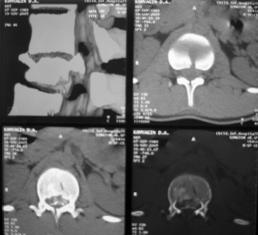

При малых сроках от момента травмы (от нескольких часов до 2-5 дней) операцию выполняли в объеме задней непрямой репозиции и стабилизации многоопорной металлоконструкцией с опорой на интактные тела позвонков в сочетании с задним локальным спондилодезом. При взрывном переломе тела одного позвонка осуществляли транспедикулярную фиксацию в пределах двух смежных позвоночно-двигательных сегментов с опорой на соседние интактные позвонки, непрямую репозицию тела сломанного позвонка. Завершали операцию формированием заднего локального спондилодеза вдоль металлоконструкции (рис. 10).

Рис. 10. Рентгенограммы пациента К. 16 лет. Взрывной перелом L1

А – КТ до операции; Б – после задней непрямой репозиции, транспедикулярной фиксации и заднего спондилодеза |